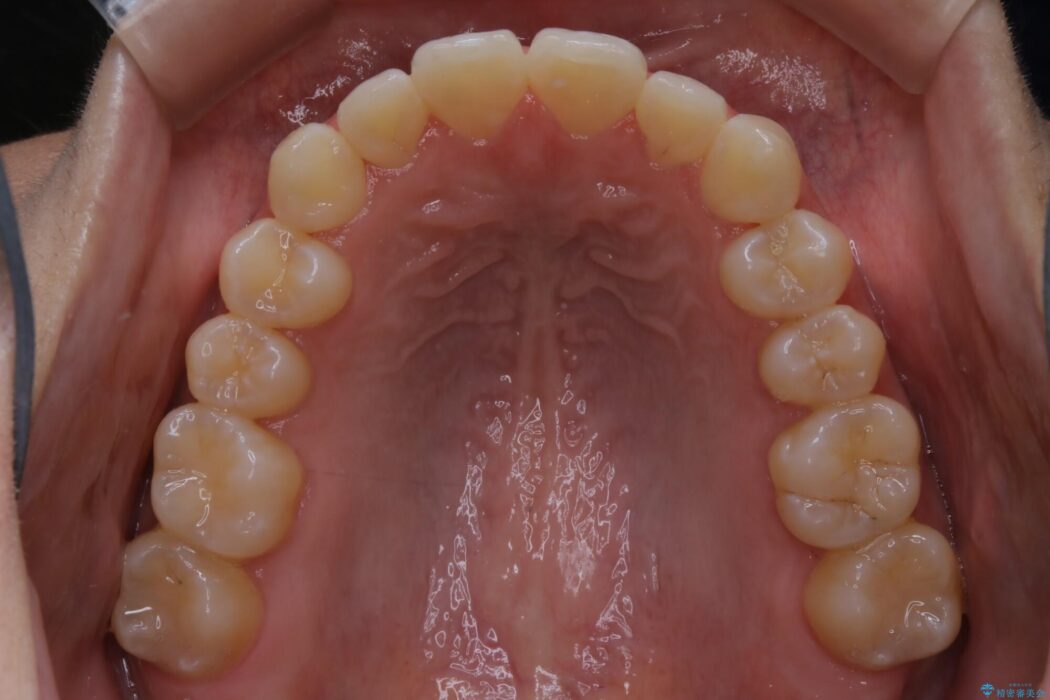

上顎歯列のガタガタを改善したいとのことで来院されました。

前歯の一部に反対咬合が見られ歯列がガタガタしていたためインビザラインでの矯正治療をご提案しました。

また、奥歯の噛み合わせなどにほとんど問題がなかったことからインビザラインのライトパッケージを選択しました。